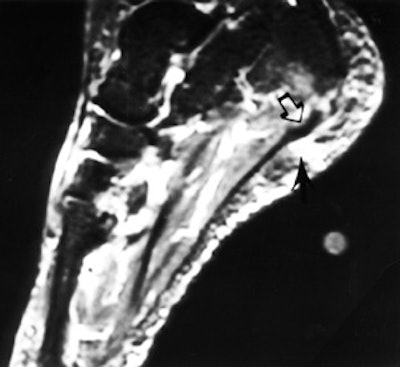

In 54 patients identified with pain at the origin of the plantar fascia, 47 had relief >50% of their pain by a single perifascial injection (figure 2).

FIGURE 2. (A) This sagittal fat-suppressed MR image shows thickening of the plantar fascia origin (hollow arrow) and edema within the fat pad (black arrow), near a skin marker.

(B) The patient undergoing a fluoroscopy-guided injection with the contrast (black arrow) tracking along the fascia origin. The patient reported complete pain relief from the anesthetic.

There were no complications from injection, though three patients reported temporary worsening of the plantar heel pain. Surgery was recommended to eight patients with recurrent pain and successful pain relief from an injection. Five patients underwent excision of the origin of the plantar fascia and have been followed a minimum of 1 year. There were no complications from the surgery and all patients reported functional improvement, though none had pain relief equal to the maximum improvement from an injection. All five surgical pathology specimens demonstrated abnormality of the fascial tissue.